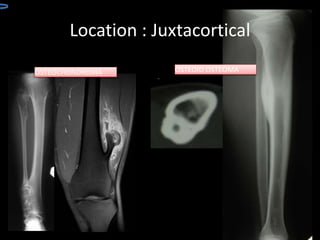

Location

Location can provides clues

to its identity

– Medullary

– Medullary eccenteric

– Cortical

– Juxtacortical

LOCATION BENIGN BONE

TUMOR

JUXTACORTICAL TUMOR

Location : Juxtacortical